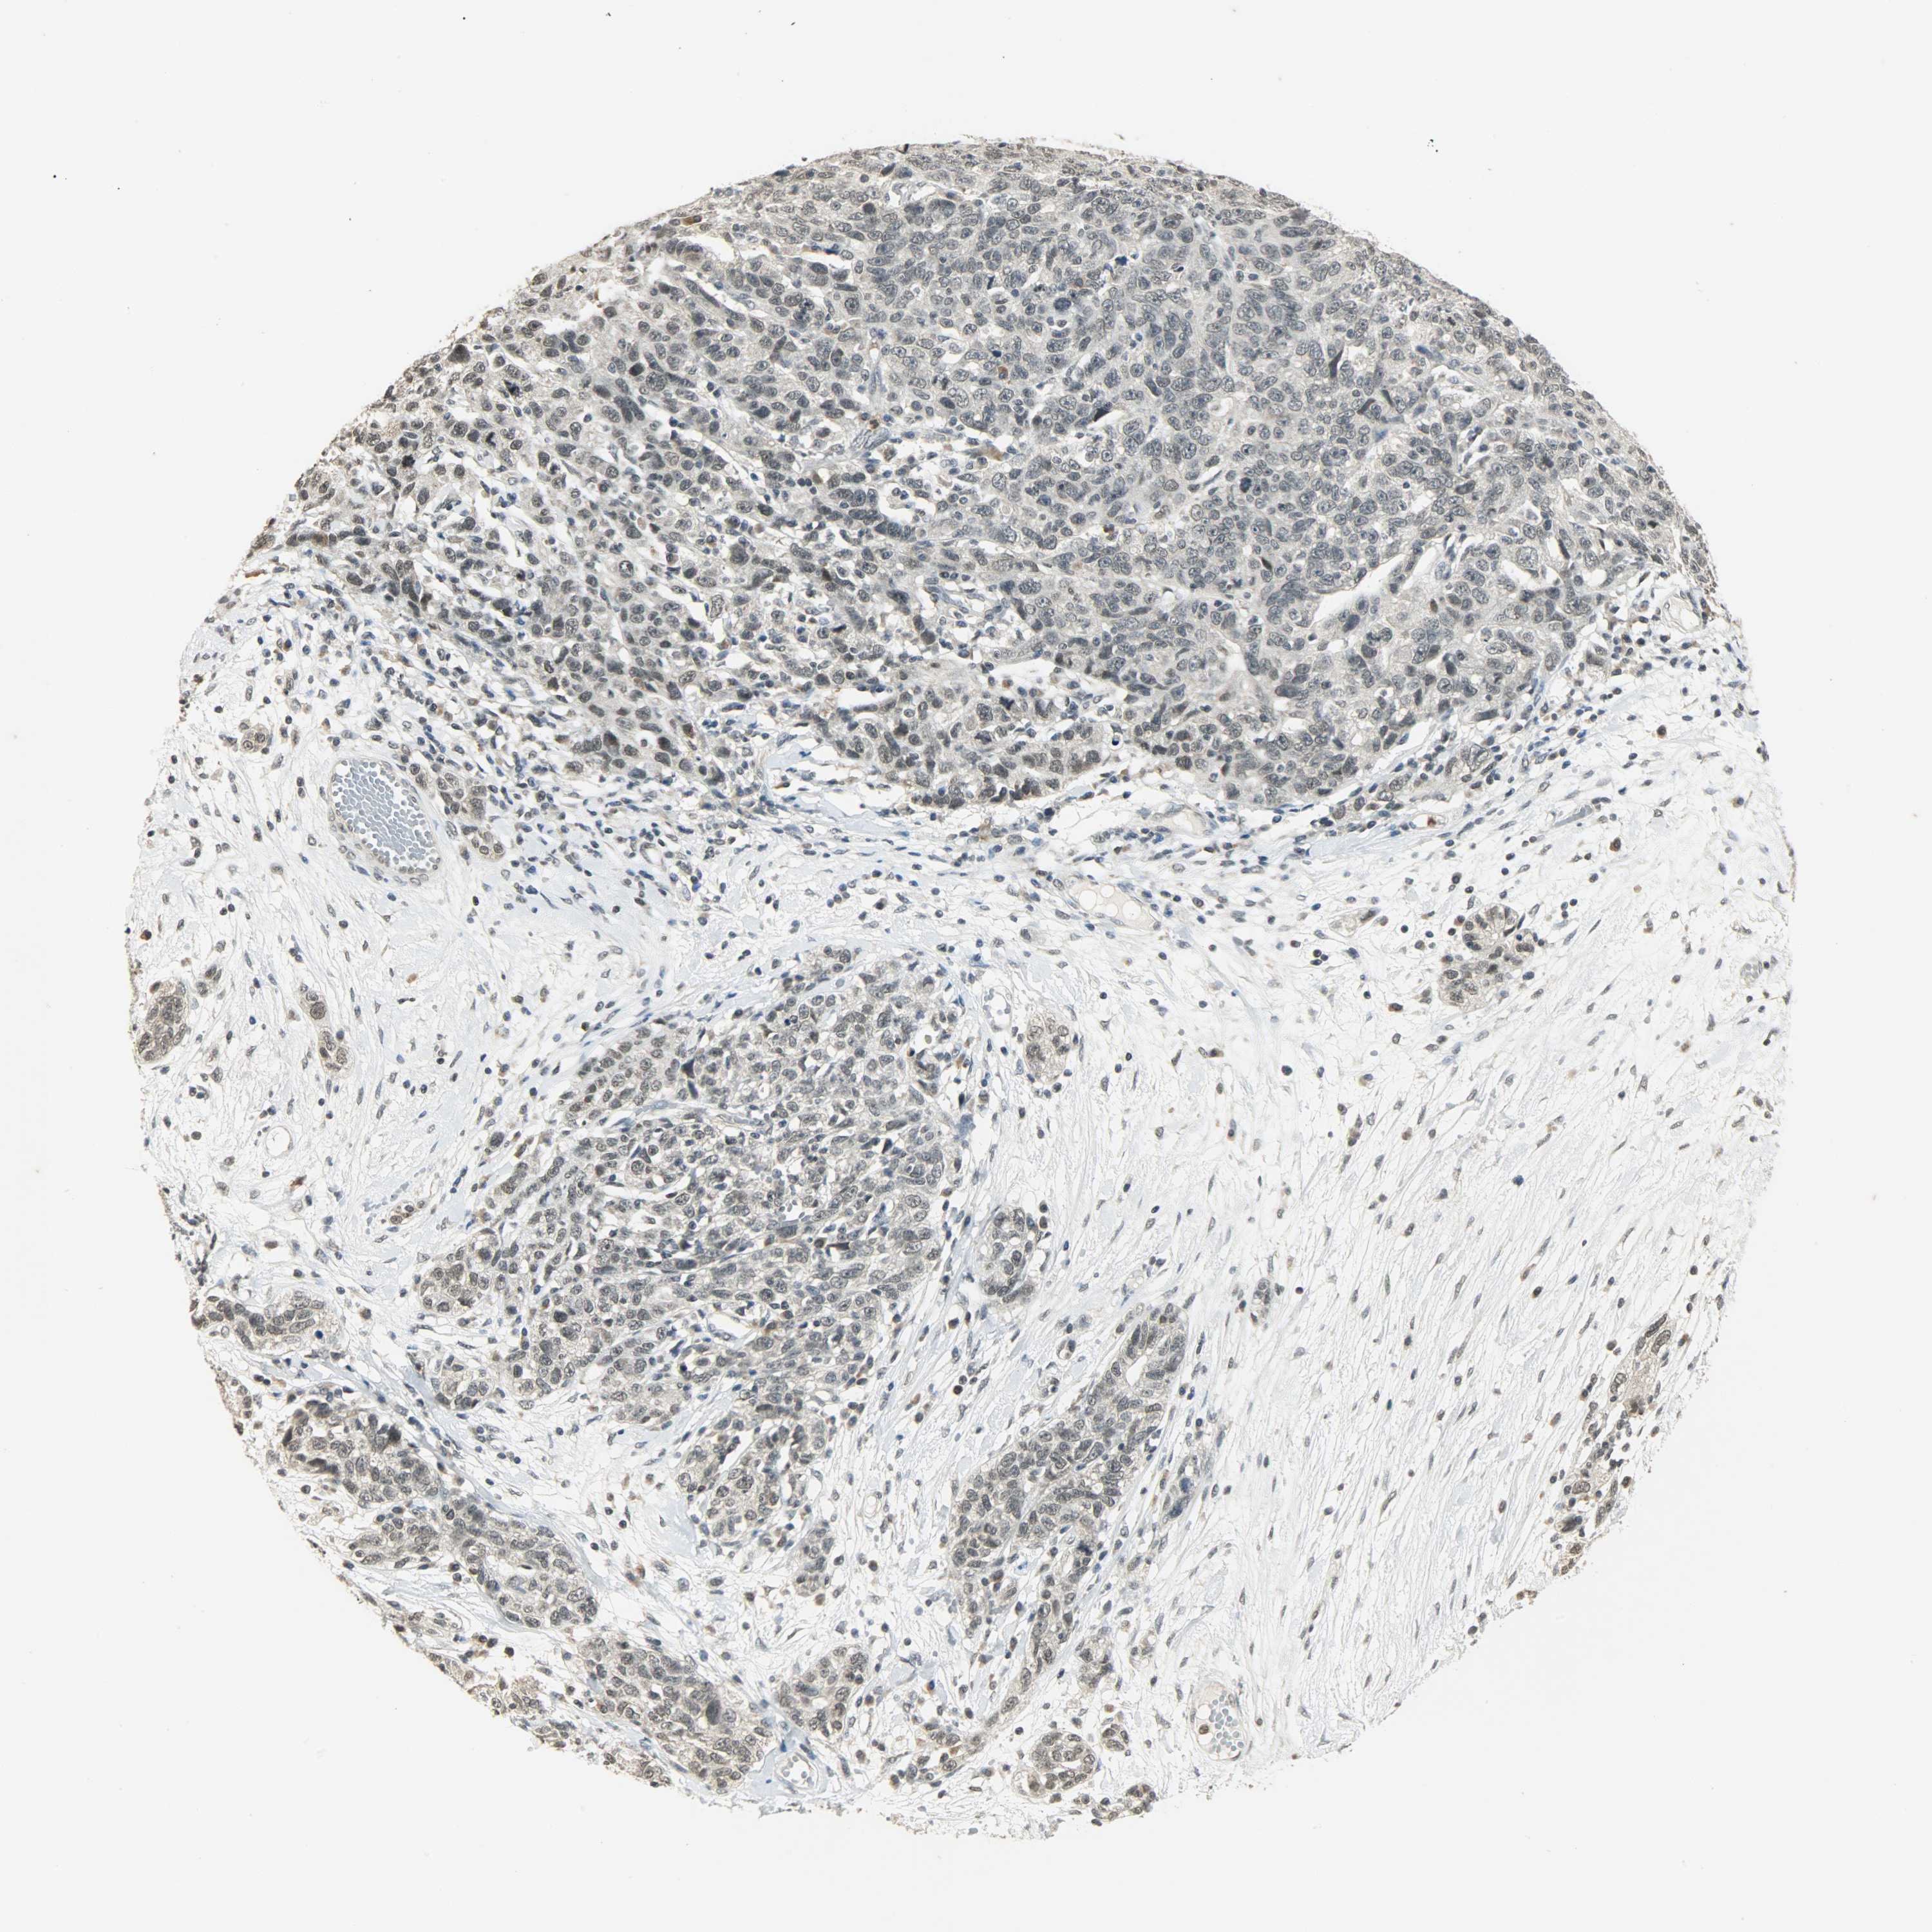

OVARIAN CANCER - Protein expressioni

A mouse-over function shows sample information and annotation data. Click on an image to view it in a full screen mode. Samples can be filtered based on level of antibody staining by selecting one or several of the following categories: high, medium, low and not detected. The assay and annotation is described here.

Note that samples used for immunohistochemistry by the Human Protein Atlas do not correspond to samples in the TCGA dataset.

Antibody stainingi

Antibody staining in the annotated cell types in the current human tissue is reported as not detected, low, medium, or high, based on conventional immunohistochemistry profiling in selected tissues. This score is based on the combination of the staining intensity and fraction of stained cells.

Each image is clickable and will lead to virtual microscopy that enables deeper exploration of all samples and also displays staining intensity scores, fraction scores and subcellular localization as well as patient and tissue information for each sample.

Antibody HPA008751

Antibody CAB005227

Carcinoma, NOS

Cystadenocarcinoma, serous, NOS